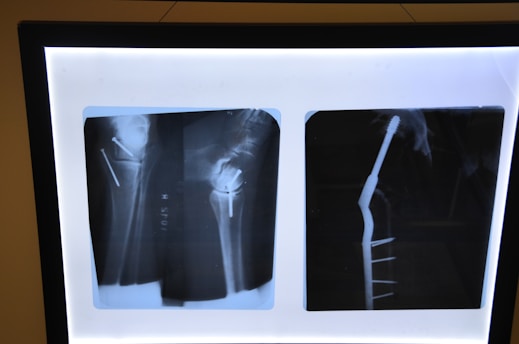

Ethoscan se especializa en soluciones de imagenología médica, combinando tecnología avanzada con formación profesional. Ofrecemos diplomados, consultoría y productos de alta calidad para optimizar el uso de resonancias magnéticas y equipos de diagnóstico en clínicas y hospitales.

Innovación en imagenología